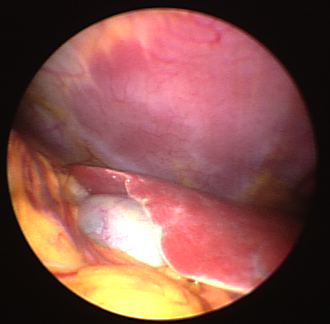

Normalbefund eines rechten Leberlappens